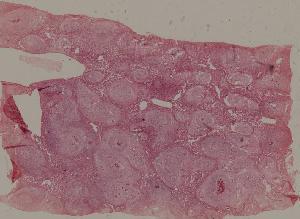

99. Experimental acute schistosomiasis of the liver (rabbit)